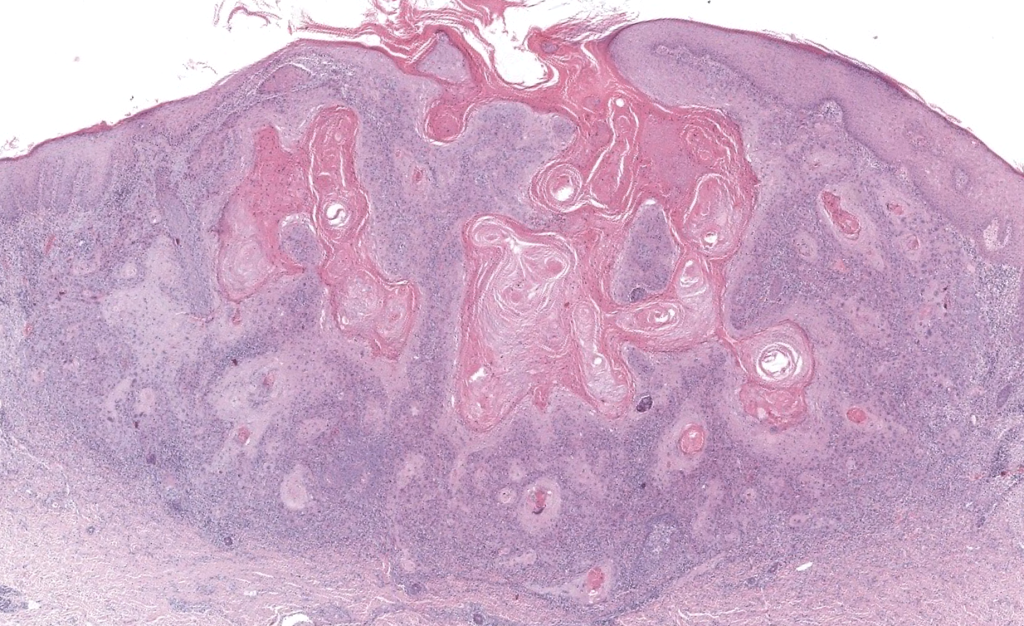

- Neoplasia maligna epitelial originada de queratinocitos epidérmicos, con distinta diferenciación escamosa, potencial de invasión local profunda y metástasis linfática/hematógena. Cassarino 2006, Motaparthi 2017

- Subtipo histológico (convencional, desmoplásico, fusocelular, verrucoso, etc.).